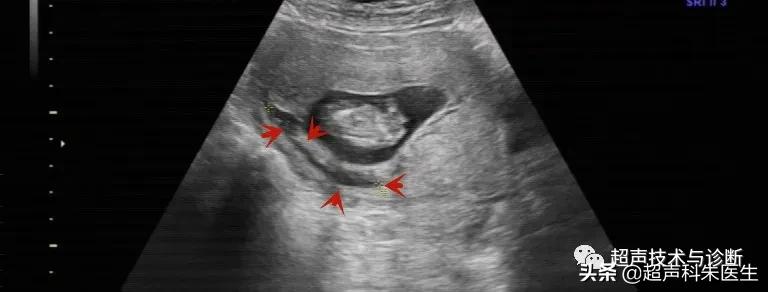

出现绒毛膜下血肿的孕妇,仅有20%会出现阴道不规则流血或下腹部疼痛的症状,而其余大多数绒毛膜下血肿是在超声检查中发现的,其超声表现为:子宫壁和胎膜(或孕囊)之间的无回声区,多位于胎盘下缘至宫颈内口间,以弧形或新月形多见,若血肿较多或血肿形成时间较长时,内可见点、絮状弱回声及条带状强回声,彩色多普勒超声检查:血肿内无血流信号。

接下来我们来看看具体病例: